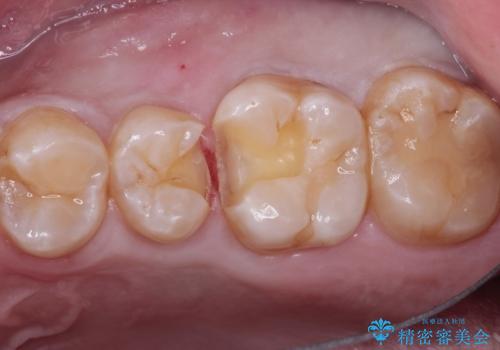

むし歯発見!e-max インレー(プレス)

- 定期健診にてむし歯を認めた患者様です。

セラミックインレーにて修復治療を行いました。

- 14万円(セラミックインレー×2)費用は治療当時の料金となります

当院でのセラミックインレーはすべてe-maxと呼ばれる高強度セラミックにて製作されます。

また、製作方法もプレスと呼ばれる方法を用いることで精度を高めています。